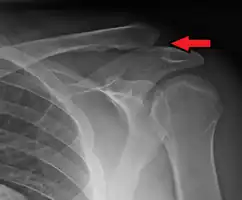

Type 3

Type 3 AC joint separation on plain X ray